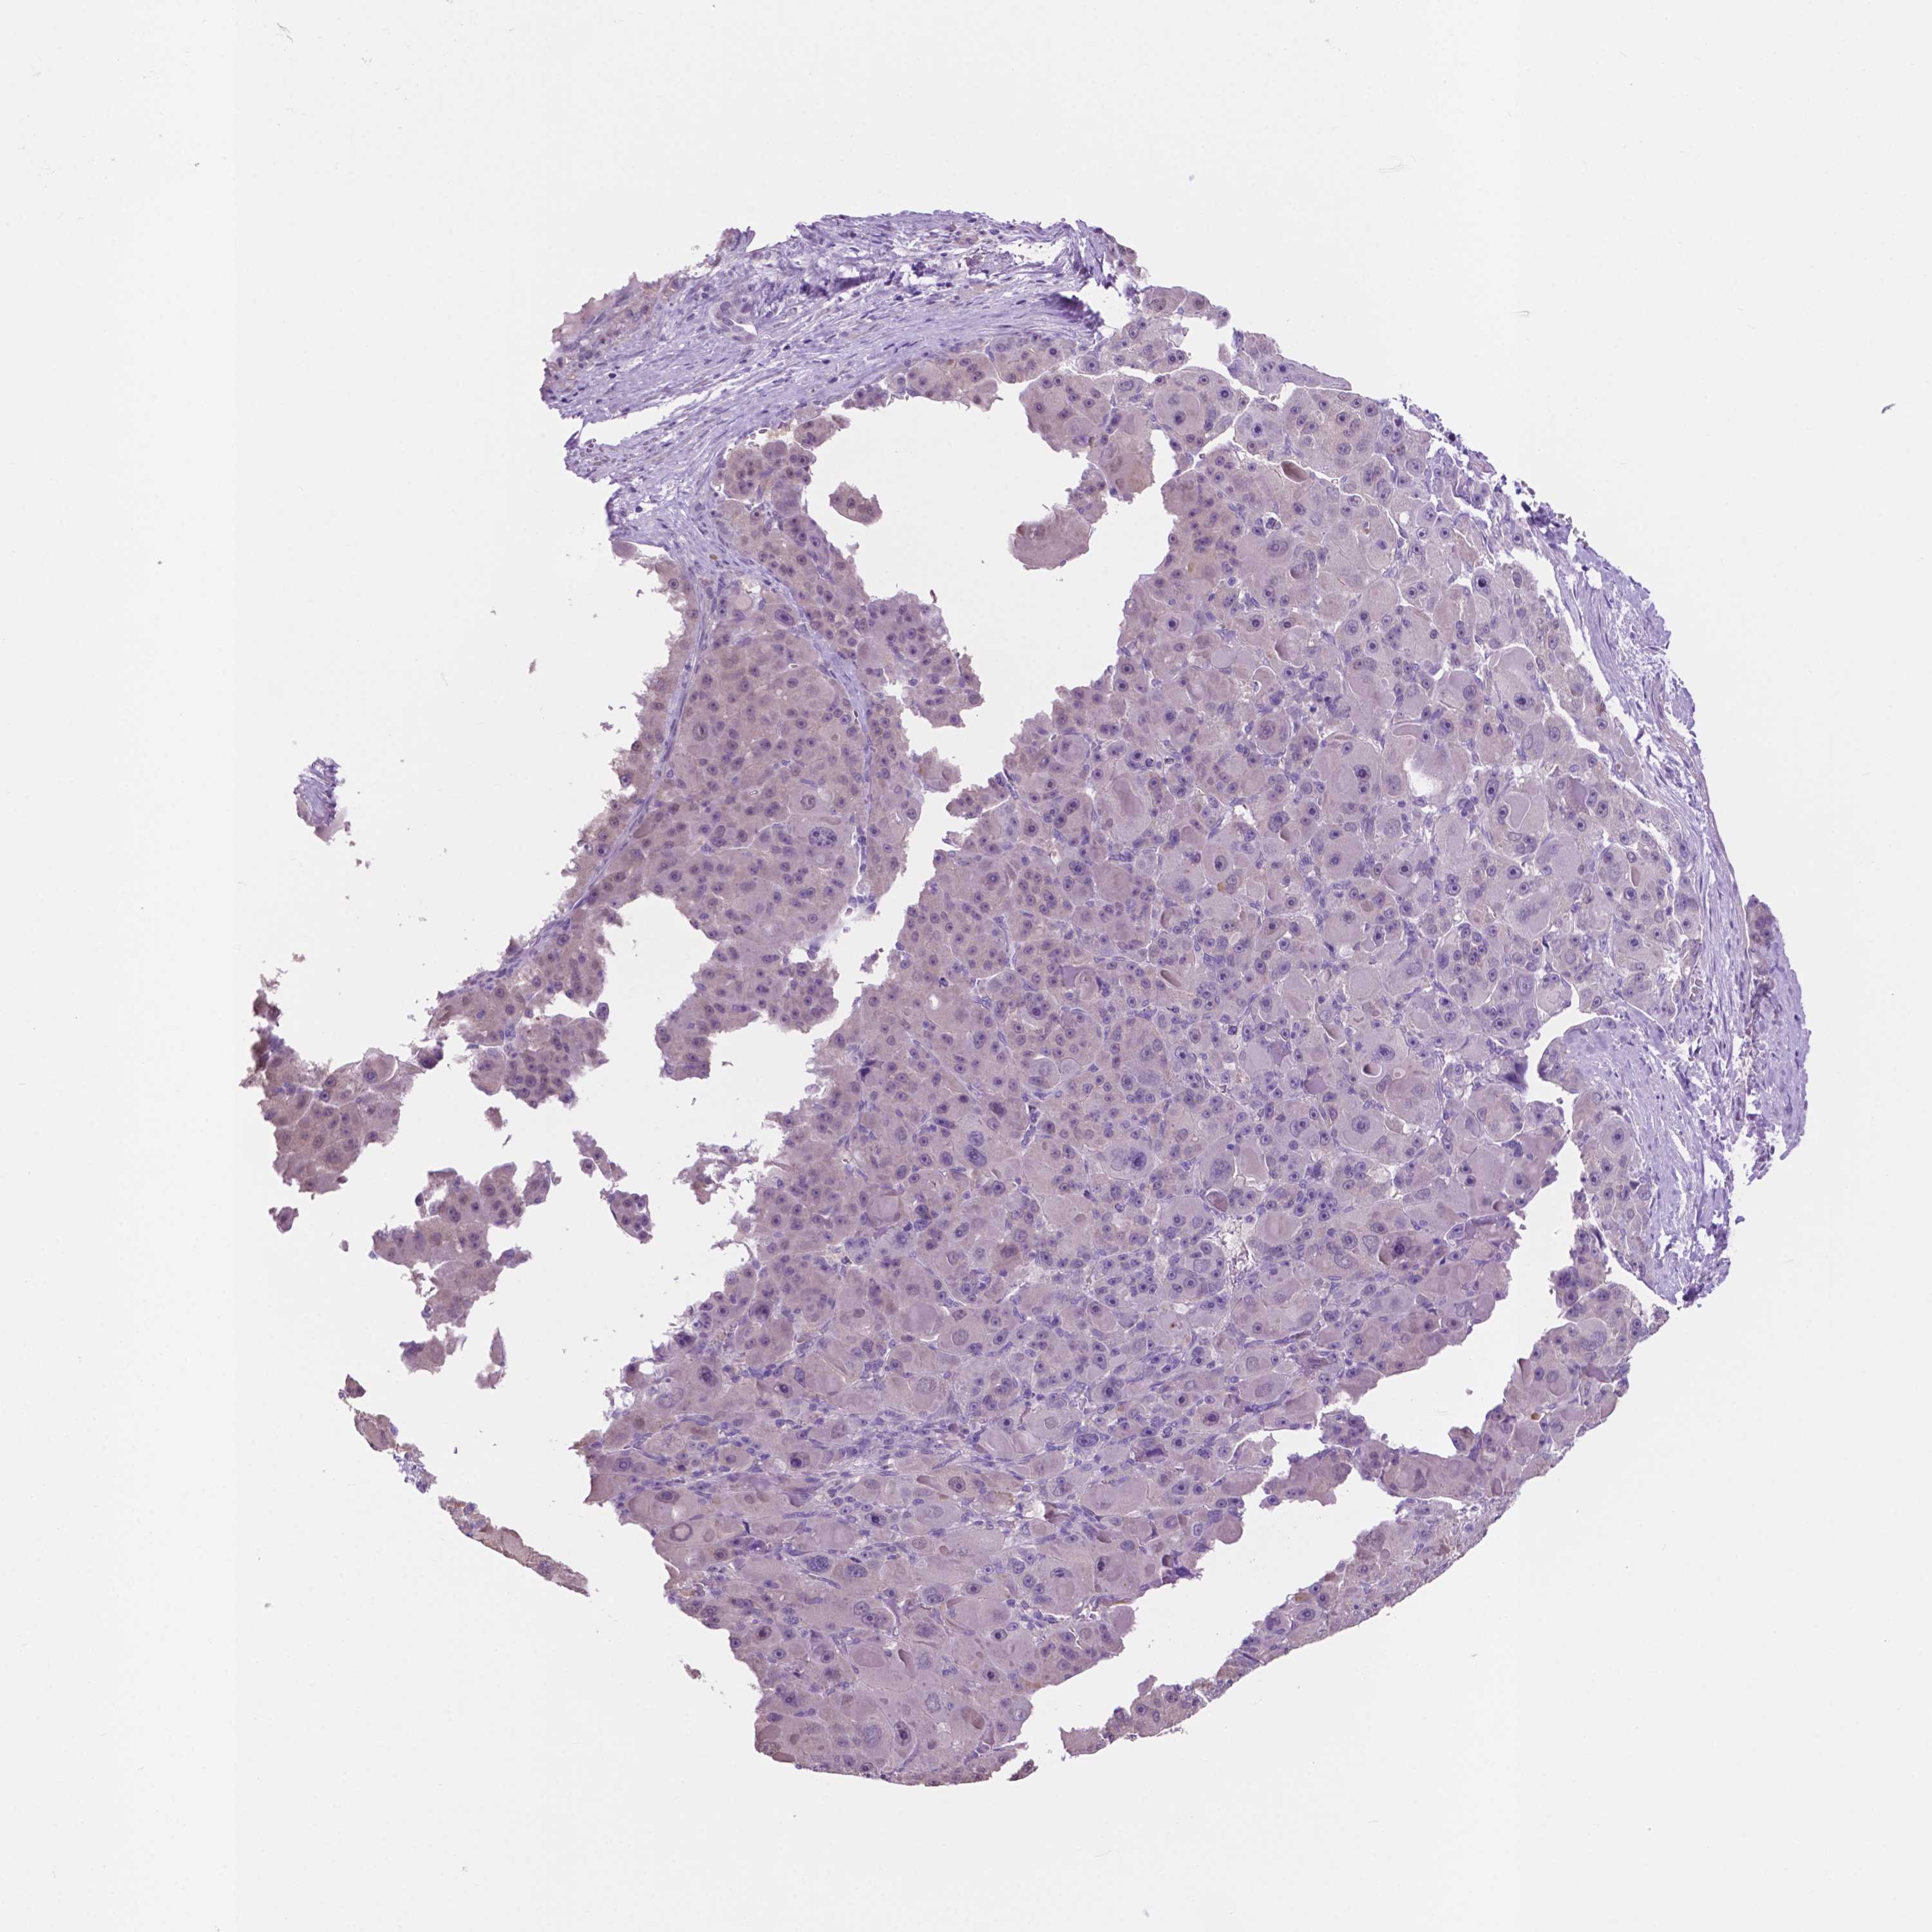

LIVER CANCER - Protein expressioni

A mouse-over function shows sample information and annotation data. Click on an image to view it in a full screen mode. Samples can be filtered based on level of antibody staining by selecting one or several of the following categories: high, medium, low and not detected. The assay and annotation is described here.

Note that samples used for immunohistochemistry by the Human Protein Atlas do not correspond to samples in the TCGA dataset.

Antibody stainingi

Antibody staining in the annotated cell types in the current human tissue is reported as not detected, low, medium, or high, based on conventional immunohistochemistry profiling in selected tissues. This score is based on the combination of the staining intensity and fraction of stained cells.

Each image is clickable and will lead to virtual microscopy that enables deeper exploration of all samples and also displays staining intensity scores, fraction scores and subcellular localization as well as patient and tissue information for each sample.

Antibody HPA039219

Antibody HPA048187

Staining

High

Medium

Low

Not detected

Intensity

Strong

Moderate

Weak

Negative

Quantity

>75%

75%-25%

<25%

None

Location

Nuclear

Cytoplasmic/membranous

Cytoplasmic/membranous,nuclear

Cholangiocarcinoma

Carcinoma, Hepatocellular, NOS